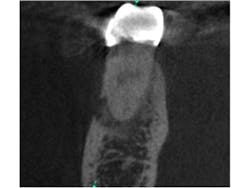

Fig. 2 is a sagittal slice through the lesion, further showing the mixed nature of the lesion. Figs. 3 and 4 are coronal and axial slices respectively. Both coronal and axial slices show that the PDL is intact around the root end and show that the lesion has caused erosion of the buccal cortical plate. Due to the unusual appearance of this lesion, an oral and maxillofacial radiologist also evaluated the CBCT scan.

Fig. 3: Coronal slice through the mesial root of tooth No. 30. Note the PDL being undisturbed around the apex and the erosion of the buccal cortical plate.

Fig. 4: Axial slice in the apical third of tooth No. 30. Note the undisturbed PDL and the mixed nature of the lesion.